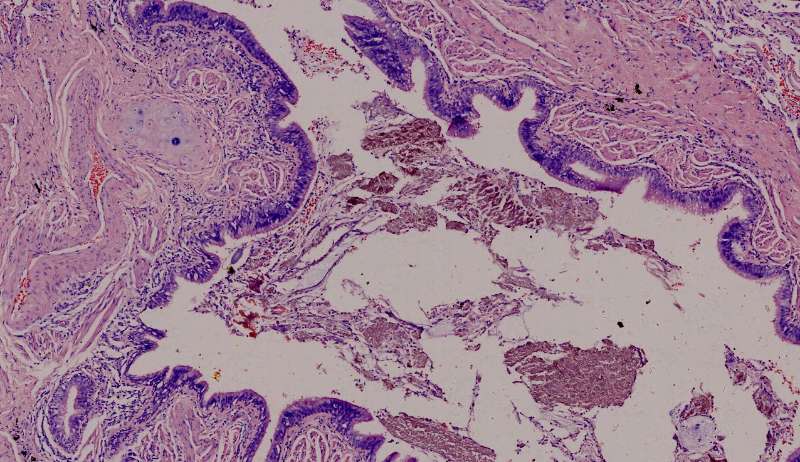

这个人的支气管腔有一大团曲霉,被冲掉了,扩张的支气管有炎症细胞浸润,还有支气管外侧,含铁血黄素沉积。

为什么有含铁血黄素呢? 曲霉菌容易使周围出现出血。太多含铁血黄素,吞不完 剩下一点曲霉菌,看看:

刚才的曲霉菌是这里?王:是的,这里有残留菌丝 第二例曲霉

曲霉菌孢子很少见到,基本都是菌丝团,这里也是支气管扩张区,菌丝团偏黄褐色,也快死了。